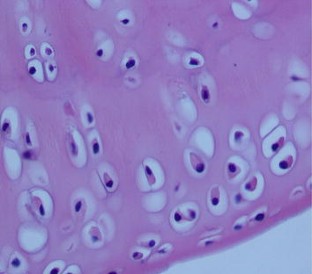

Observe pulse electromagnetic fields (PEMFs) effects on ovariectomized (OVX) rats, to study the mechanisms of PEMFs therapy for postmenopausal osteoarthritis. Forty-eight female rats were exposed to PEMFs (PEMFs group), administrated E2 and placebo PEMFs (E group), or were treated with placebo PEMFs (OVX and Sham groups). The treatment duration was 30 days after which serum E2 levels, chondrocyte morphology, chondrocyte apoptosis and matrix metalloproteinases-13 expression in knee joint was analyzed. We observed differential chondrocyte formation in each group, and serum E2 content in the PEMFs and E group were significantly higher than the OVX group. The apoptosis index of chondrocytes and the positive index of MMP13 expression in the PEMFs group and E group were significantly lower than the OVX group. PEMFs has a systemic effect on estrogen metabolism in ovariectomized rats, then inhibit chondrocyte apoptosis and downregulate MMP13 expression of knee joint cartilage. It may be the mechanisms by which PEMFs therapy works for on postmenopausal osteoarthritis.

Fig. 1

Fig. 2

Fig. 3

Fig. 4

Fig. 5

Fig. 6

Fig. 7

Fig. 8

Fig. 9

Fig. 10

Fig. 11

Fig. 12